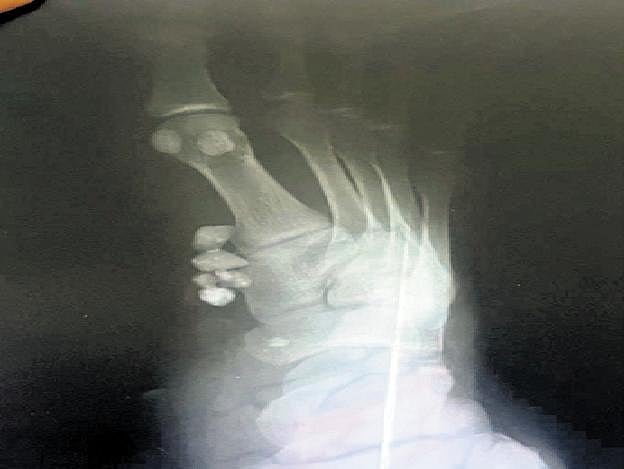

X-ray revealing stones within the stitched portion | Express

After getting the wounds cleaned and stitched, Mathivanan left the hospital. However, with the affected leg developing pain despite treatment, he consulted a private hospital in Aranthangi on Saturday. X-rays taken there revealed stones inside the leg, near to the wounded patch, Mathivanan said, and alleged the general hospital in Aranthangi of negligence for stitching the wound without removing the stones.

"The private hospital staff told me that the stones may affect the entire leg if not removed in time," Mathivanan said. Subsequently, all the stones were successfully taken out from the leg, sources said. The news about the incident swiftly spread across the locality, leading to public outrage, sources said.